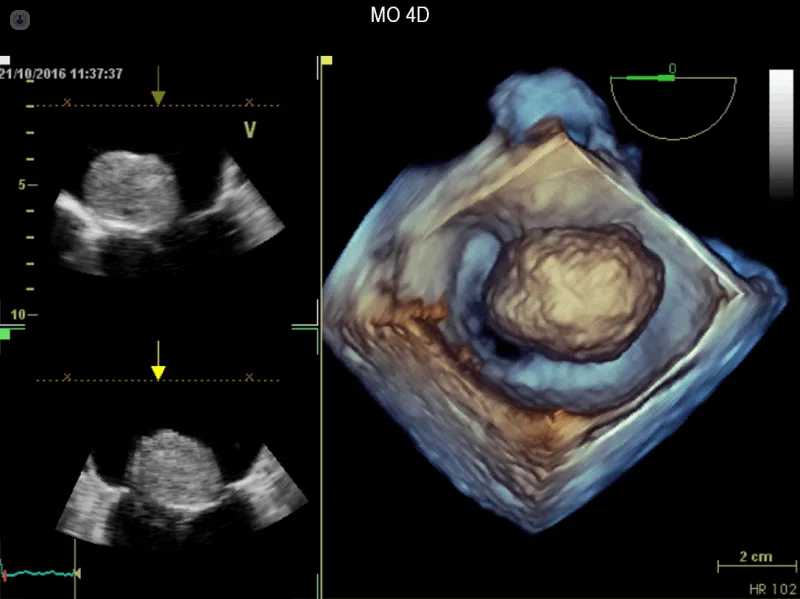

- اکوکاردیوگرافی سه بعدی

اکوکاردیوگرافی 2 بعدی

این تکنیک برای دیدن ساختارهای واقعی و حرکت ساختارهای قلب استفاده می شود. یک نمای اکو دو بعدی به شکل مخروطی روی مانیتور به نظر می رسد و می توان حرکت لحظه ای ساختارهای قلب را مشاهده کرد. این به پزشک امکان میدهد تا ساختارهای مختلف قلب را در حال کار ببیند و آنها را ارزیابی کند.